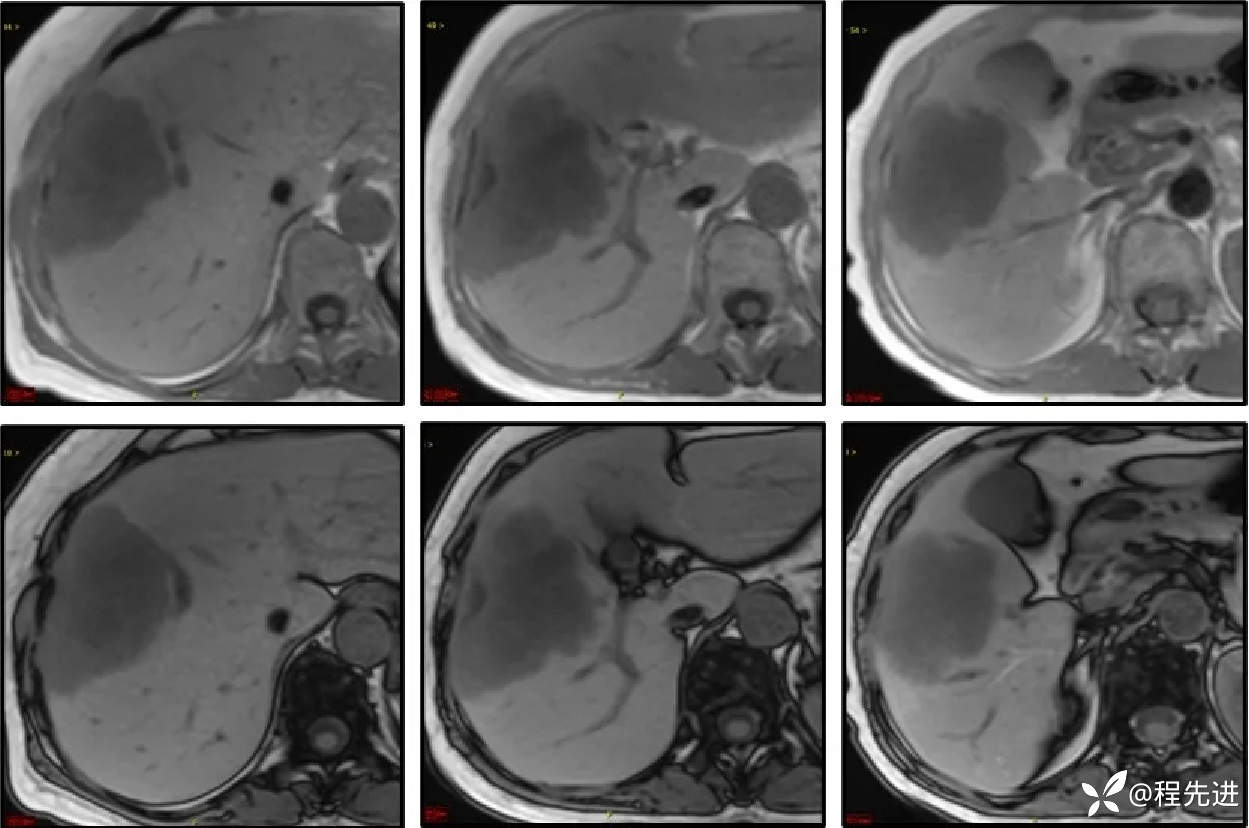

同反相位:

T2: